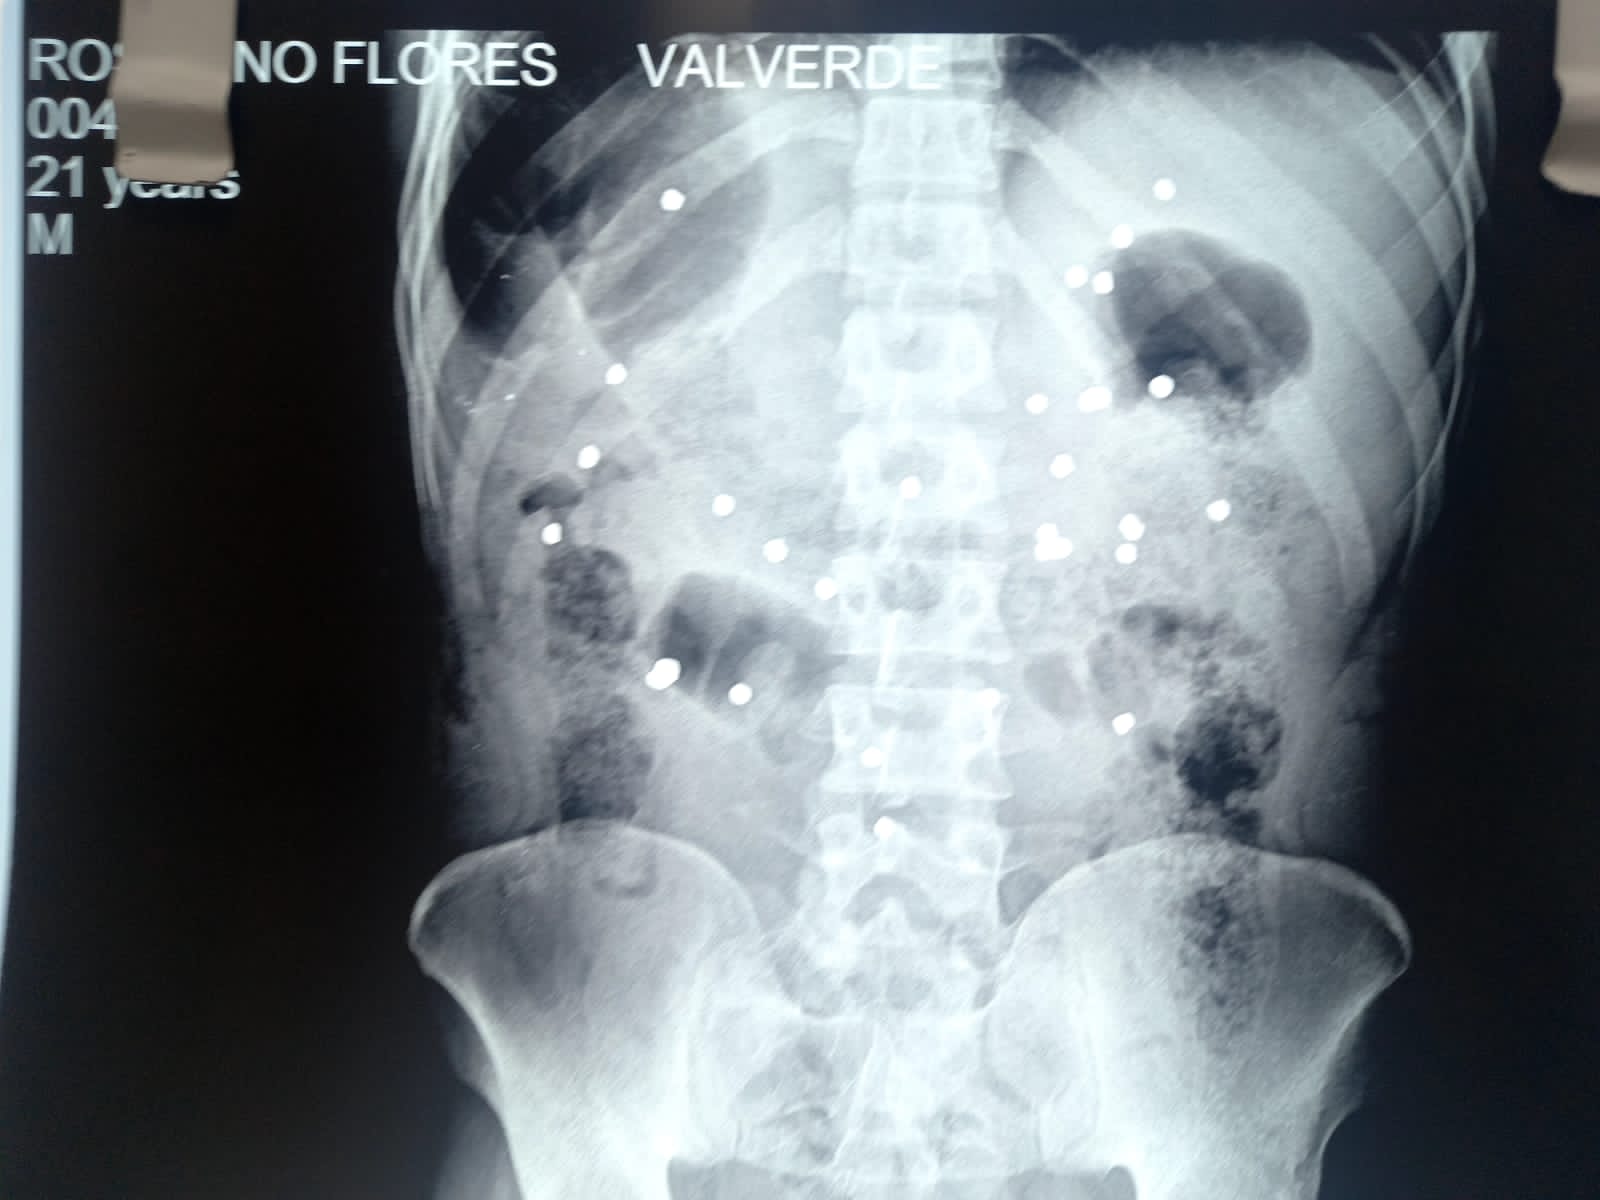

202304americas_peru_rosalino_xray

X-ray showing pellets in the body of Rosalino Florez.